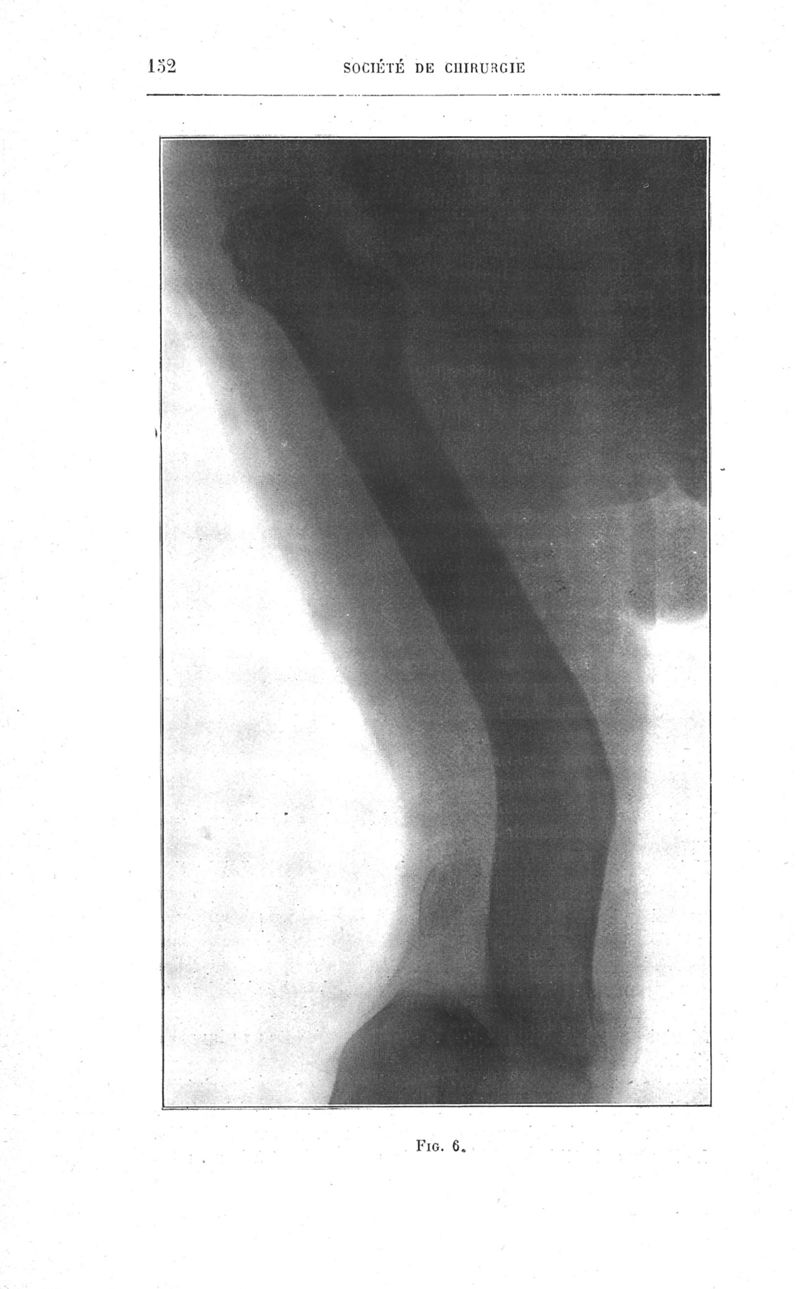

Bulletins et mémoires de la société de chirurgie de Paris

Tome XXXIX, 1913. - Paris : Masson, 1913.